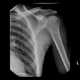

Osteopoikilosis